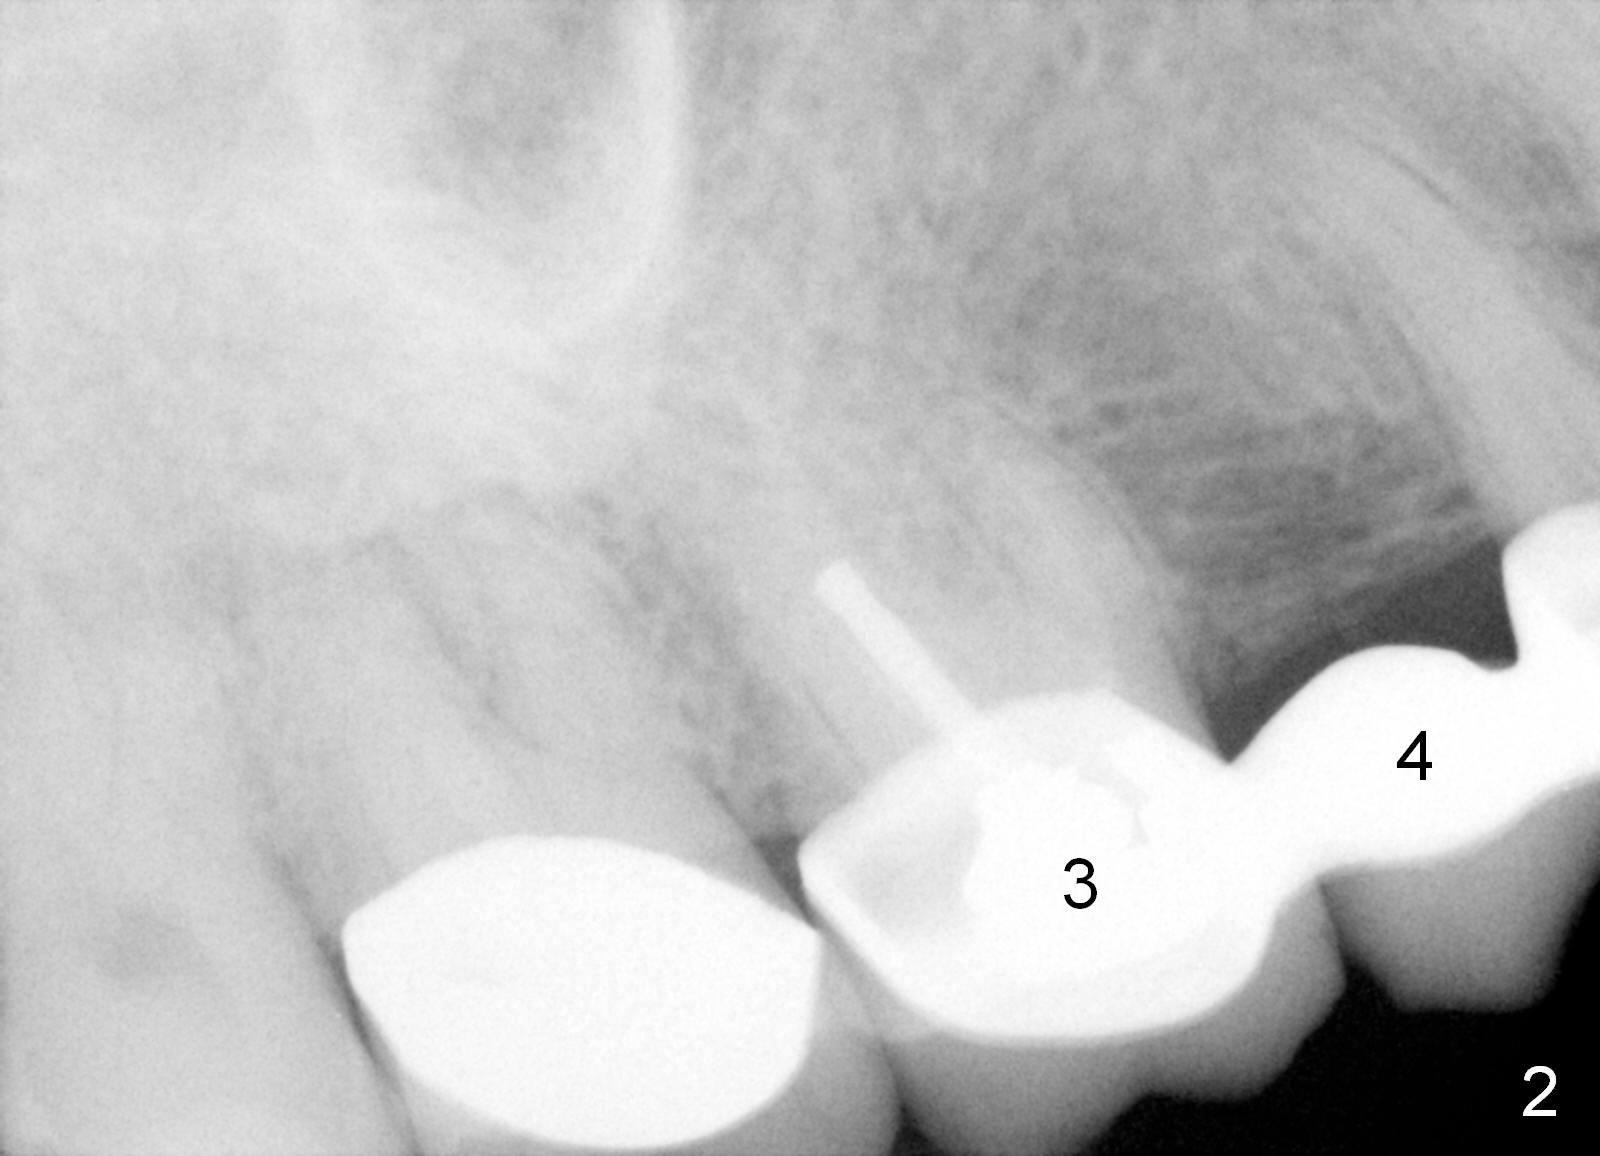

A 59-year-old lady had a brain stem tumor removed ~ 20 years ago. The surgery left her tongue paralyzed (cranial nerve #12). She mainly chews on the right side. Porcelain has been chipped from #2 crown and #3 retainer. Treatment plan includes removal of #4 pontic (Fig.2 CT coronal section (B: buccal)), implant placement (Fig.1), and crown placement at #2-4 once the implant osteointegrates. Since the ridge at #4 is narrow buccopalatally, a 3 mm 1-piece angled (15°) implant is to be placed. Use the corresponding 3 mm tissue punch for access after palpation of the ridge. Bone density in the area is low (-300 to 300 Hounsfield units). Underprep is a must.